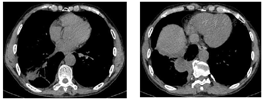

胸部CT(图2、图3):右肺下叶团块状影伴液化坏死,考虑感染(肺脓肿可能),不除外肿瘤;双肺下叶散在感染灶;右侧胸膜增厚,右侧胸腔积液,部分包裹;纵隔淋巴结肿大。床旁心电图:窦性心律,正常心电图。红细胞沉降率82 mm/h;血常规:白细胞计数22.66×109/L,中性粒细胞绝对值19.66×109/L,淋巴细胞绝对值0.72×109/L,嗜酸细胞绝对值0×109/L,血红蛋白121 g/L,中性粒细胞百分率86.8%;C反应蛋白343.78 mg/L;肝功能:谷丙转氨酶19 U/L,谷草转氨酶36 U/L,白蛋白38.7 g/L,前白蛋白93 mg/L,间接胆红素18.6 umol/L,直接胆红素13.7 umol/L,总胆红素32.3 umol/L;肾功能正常;血钠133.3 mmol/L;随机血糖7.87 mmol/L;凝血功能:纤维蛋白原降解产物5.5 μg/ml,血浆纤维蛋白原8.8 g/L,D-二聚体0.97 mg/L;血气分析(吸氧2 L/min):酸碱度7.47,氧分压81 mmHg,二氧化碳分压39.3 mmHg,剩余碱4.1 mmol/L,氧饱和度96.6%;降钙素原2.65 ng/ml;心肌梗死标志物、N-末端脑钠肽前体、肺肿瘤标志物、感染性疾病筛查未见异常;2019新型冠状病毒核酸阴性;常见呼吸道病原体抗体阴性;G试验阴性;痰涂片查结核、真菌阴性;痰、血培养阴性。

初步诊断:右下肺脓肿,右侧包裹性胸腔积液,支气管哮喘。给予头孢哌酮舒巴坦(3 g,1次/12h)静脉滴注抗感染,同时予吸氧、解痉平喘、止咳祛痰、补液、营养支持等对症治疗。为除外肿瘤和结核,于11月1日行支气管镜检查,见右肺下叶段支气管黏膜充血肿胀,可见散在黄褐色黏痰;在右肺上叶前段、右肺下叶行支气管肺泡灌洗。肺泡灌洗液涂片:上皮细胞≤10/LP、白细胞≥25/LP,G+杆菌1+,G—杆菌1+,查见少量G—双球菌,结核分枝杆菌复合群阴性,未查见抗酸杆菌和真菌。肺泡灌洗液培养:铜绿假单胞菌,对头孢哌酮舒巴坦敏感。复查红细胞沉降率94 mm/h;血常规:白细胞计数22.41×109/L,中性粒细胞绝对值19.07×109/L,淋巴细胞绝对值0.84×109/L,血红蛋白109 g/L,中性粒细胞百分率85.1%;C反应蛋白360.21 mg/L;降钙素原1.25 ng/ml。患者痰量较前增加,呈腥臭味,血液炎症指标仍高,联用克林霉素(0.6g,1次/8h)静脉滴注以覆盖厌氧菌,并再次送检痰培养,仍呈阴性。完善胸部彩超检查示:左侧胸腔肋膈角探及间距约1.3 cm无回声区,右侧胸腔探及范围约5.8 cm×10.8 cm液性暗区反射,其内可见蜂窝状稍强回声分隔,透声差;另于穿刺点处探及范围约6.6 cm×2.9 cm液性暗区反射,进针深度约2.8 cm;右肺组织内探及多处液性暗区反射,其内透声差,可见絮状低回声漂浮,较大范围约7.9 cm×4.9 cm;提示双侧胸腔积液(右侧包裹性),右肺超声所见考虑肺脓肿。因进针深度不够,床旁胸腔穿刺失败。于11月2日在超声引导下行胸腔穿刺术,胸水常规:深黄色、浑浊胸水,无凝块,白细胞总数45660 ×106/L,单个核细胞25%,多个核细胞75%,红细胞30×109/L,李凡他实验+++;胸水生化:白蛋白29.6 g/L,球蛋白25.6 g/L,总蛋白55.2 g/L,淀粉酶30 U/L,葡萄糖0.31 mmol/L,乳酸脱氢酶2427 U/L,腺苷脱氨酶72 U/L;胸水培养(需氧菌+厌氧菌)阴性。胸水检验结果支持脓胸。胸部增强CT(图4,图5,图6):右肺下叶团块状影,考虑肺脓肿,伴脓胸形成,建议治疗后复查除外肿瘤;双肺下叶散在感染灶,较前加重;右侧胸膜增厚,右侧胸腔积液,部分包裹;纵隔淋巴结肿大。